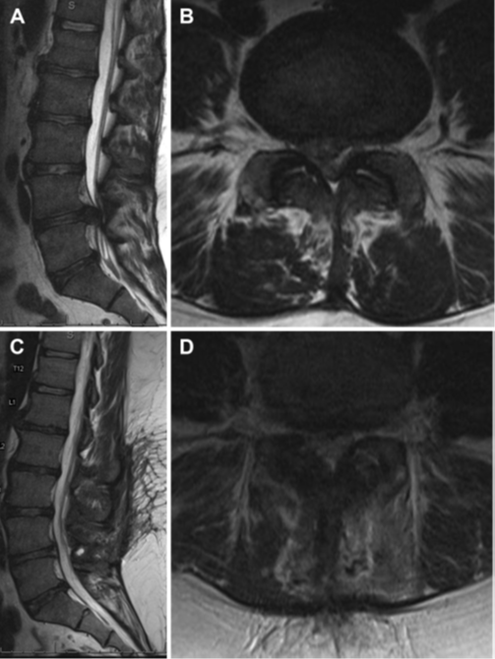

Bn nam, 25 tuổi, đến khám trong bối cảnh xuất hiện đau lưng cấp tính, nặng lên trên nền đau lưng mạn tính, đồng thời có dị cảm ở háng và chân phải, đau ở chân bên phải dọc theo vùng do rễ L4 chi phối tăng lên, giảm nhu động ruột, và bàng quang còn nước tiểu sau tiểu tiện (incomplete voiding). Khám cho thấy sức cơ động tác gập cổ chân (dorsiflexion) và duỗi cổ chân (plantar flexion) là 4/5 ở hai bên, thay đổi cảm giác ở vùng đáy chậu, nhưng trương lực cơ trực tràng bình thường. Huyết áp là 121/70, áp lực động mạch trung bình là 87, nhịp tim 64/phút, Sa O2 là 94%. BN được chụp MRI và có hình ảnh như sau (hình 1)

Hình 1. Lát cắt dọc qua đường giữa (A) và ngang (B) trên chuỗi xung T2 ở vùng cột sống thắt lưng cho thấy thoát vị đĩa đệm cạnh trung tâm ở L4/L5 gây chèn ép chùm đuôi ngựa. Hình ảnh cắt dọc qua đường giữa (C) và ngang (D) trên chuỗi xung T2 sau mổ lấy khối thoát vị cho thấy chùm đuôi ngựa được giải ép rõ.